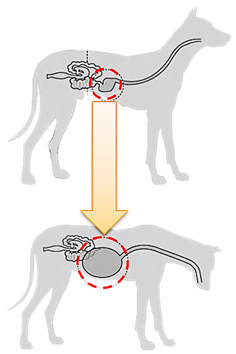

위확장-화전증후군(GDV)은 개, 고양이, 소, 말, 돼지 등의 동물에서 발생하는 위장관 질환의 하나로 주로 대형견에서 발생한다.

위 염전 증후군은 어떤 원인으로 인해 위장에 갑자기 가스가 차서 위장이 회전하고 비틀어 위장이나 주변 장기의 혈류를 차단하여 혈액 순환이 불가능하게 되어 발생합니다. 심한 경우에는 주변 장기의 괴사가 진행될 수 있으며 팽창된 위가 횡경막을 압박하여 호흡이 곤란해집니다. 심한 경우 사망에 이르는 치명적인 질병이다.

실제로는 위가 180도 회전하면서 간과 비장까지 뒤틀려 상태가 급격하게 악화돼 거의 목숨을 잃을 뻔했다.

위 염전 증후군의 치료는 가능한 한 빨리 수술하는 것입니다. 단순히 배에 가스가 찬 경우에는 내시경으로 간단히 가스를 제거하면 혈액순환이 회복된다. 그러나 배가 뒤집히면 그때부터 개의 생사의 문제가 된다. 위가 돌아오면 병원에서는 단순히 가스를 빼는 것이 아니라 배를 열어 가스를 제거한 뒤 위를 원래 위치로 되돌린 뒤 위를 복벽에 고정하는 수술을 해서 재발을 방지해야 한다.

위가 심하게 변하면 간과 비장이 함께 꼬이게 되는데 이때 혈류가 막히는 간쪽에 울혈이 생기고 이를 제거하는 수술을 하는 경우도 있다.